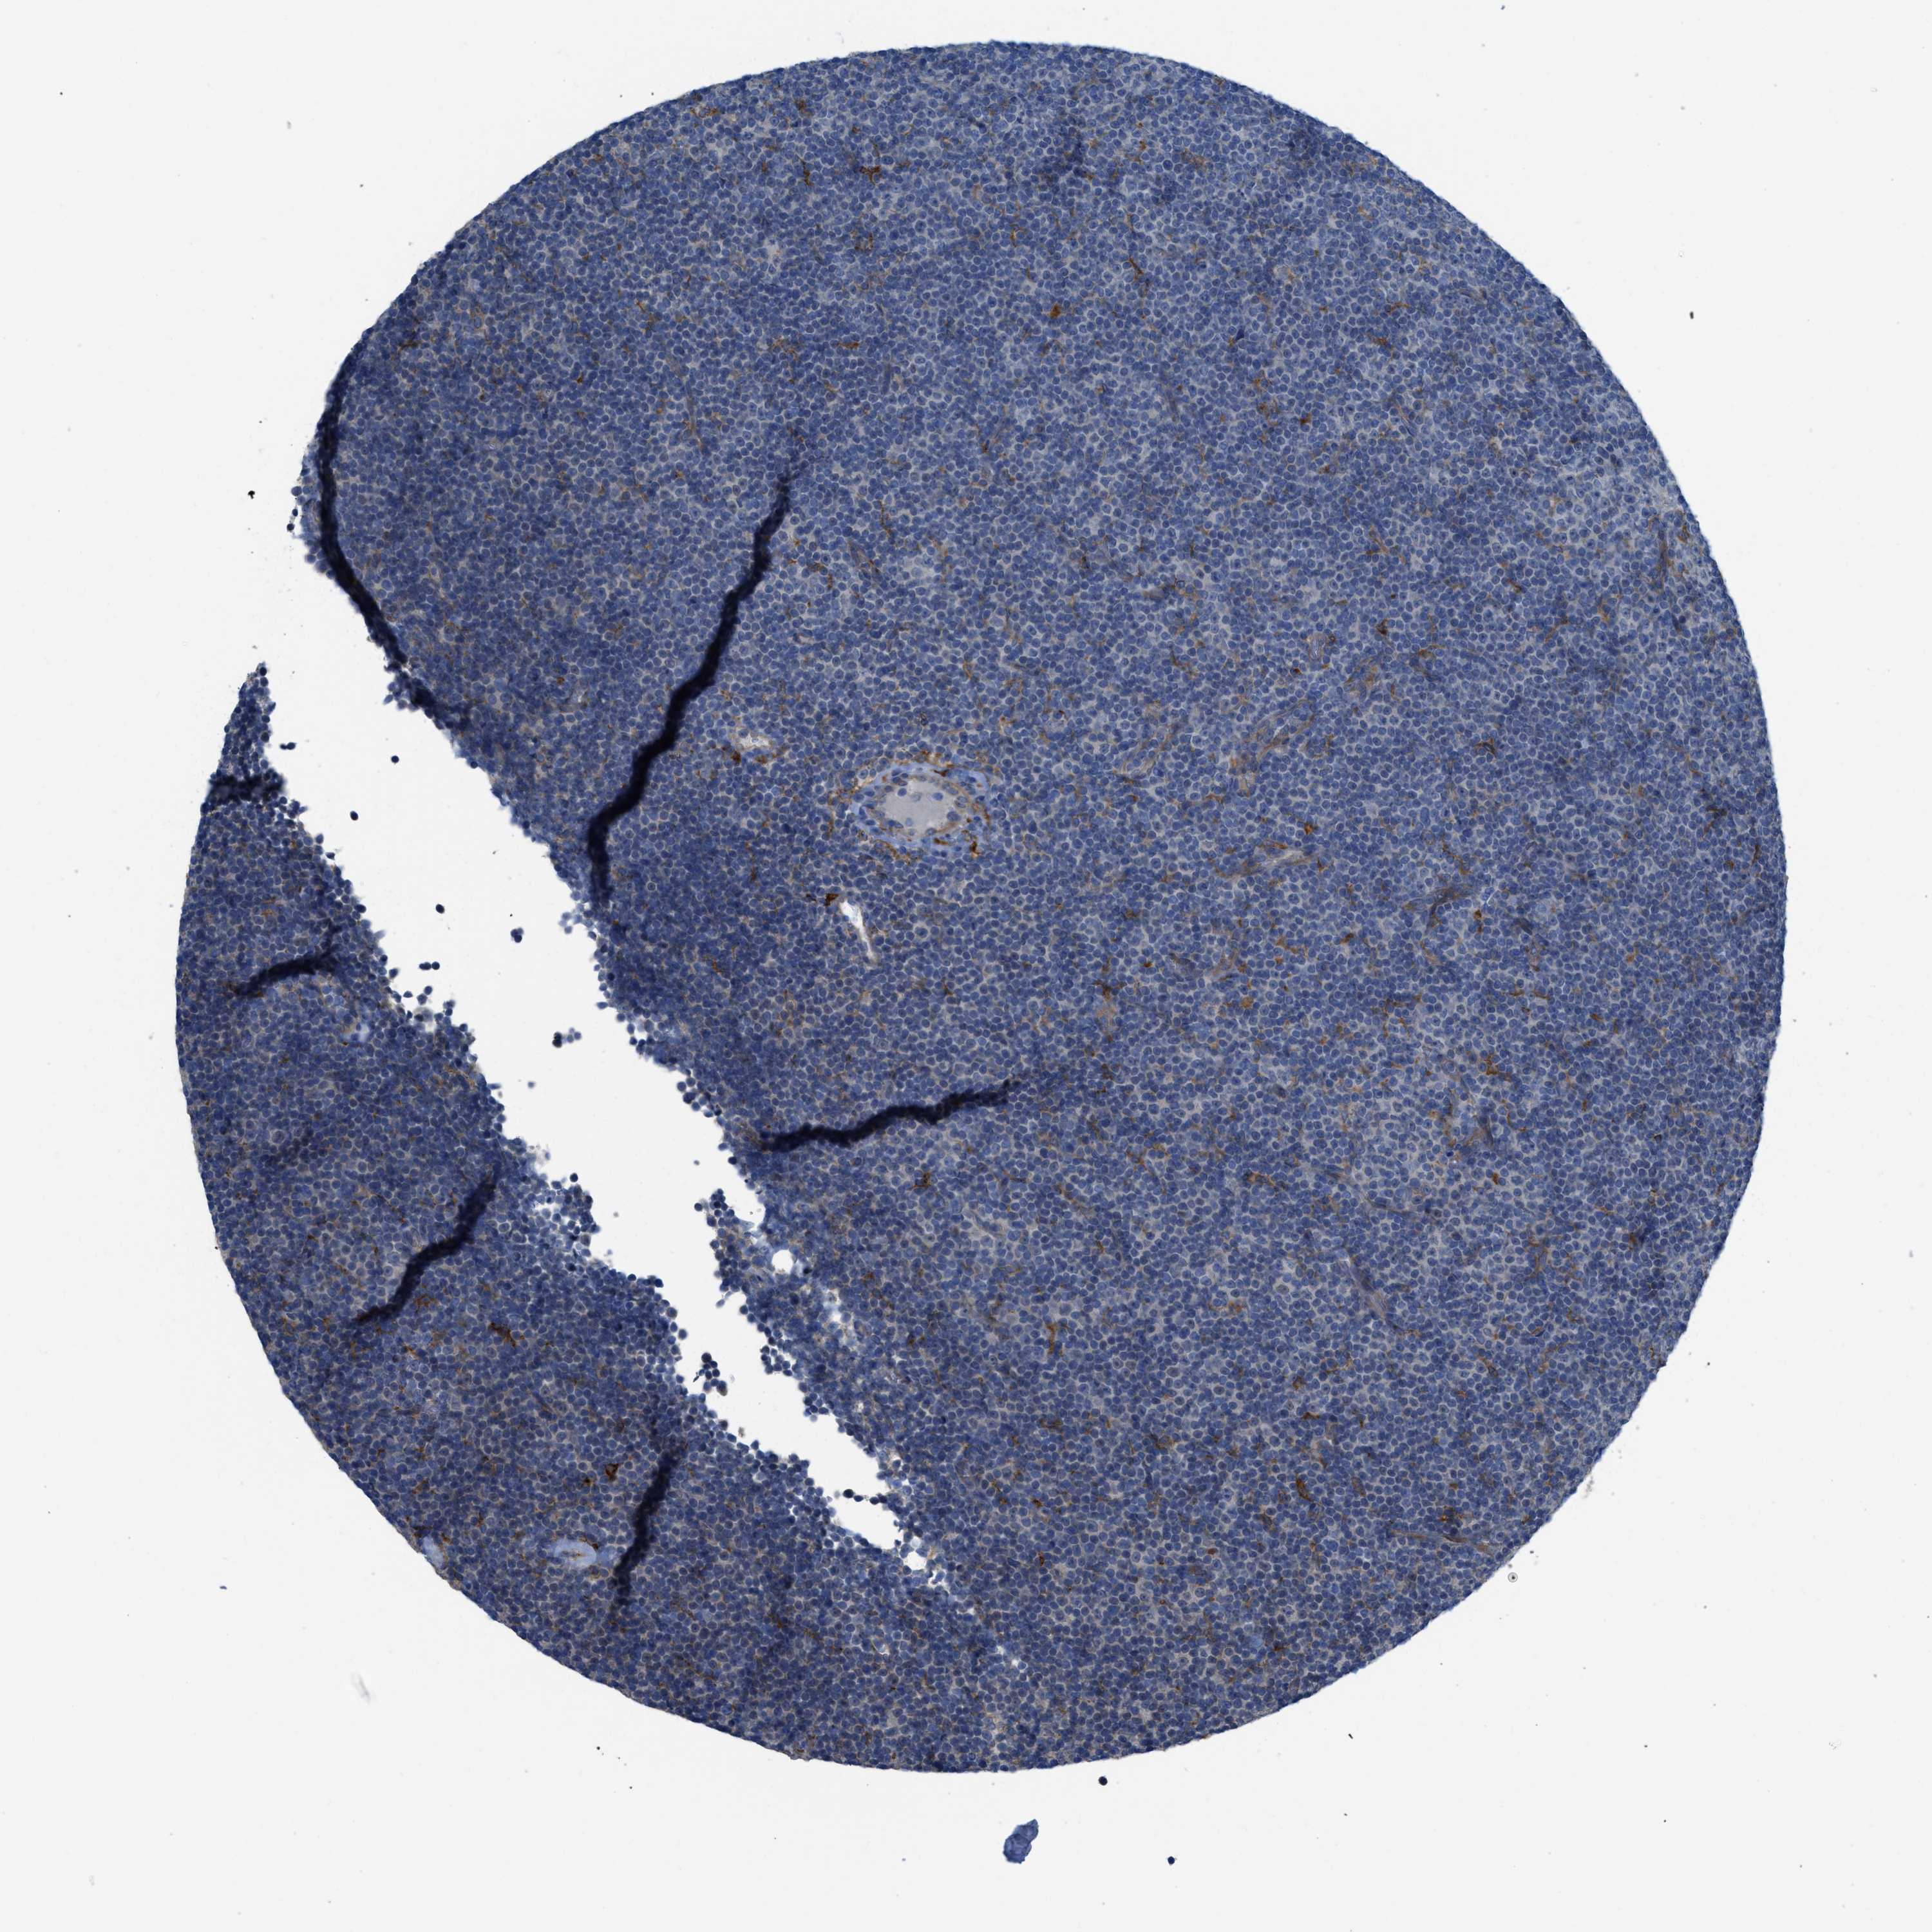

CANCER LYMPHOMA Show tissue menu

LYMPHOMA - Protein expressioni

A mouse-over function shows sample information and annotation data. Click on an image to view it in a full screen mode. Samples can be filtered based on level of antibody staining by selecting one or several of the following categories: high, medium, low and not detected. The assay and annotation is described here.

Each image is clickable and will lead to virtual microscopy that enables deeper exploration of all samples and also displays staining intensity scores, fraction scores and subcellular localization as well as patient and tissue information for each sample.

Malignant lymphoma, non-Hodgkin's type, High grade

Hodgkin's disease, NOS

Malignant lymphoma, non-Hodgkin's type, Low grade